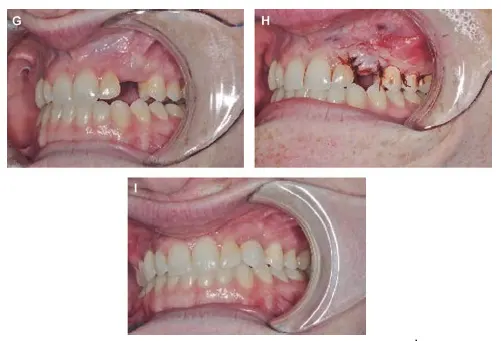

Healed implant site شکل VIII‑2 (ادامه). نمای مراحل ترمیم

G: محل ایمپلنت پس از ترمیم کامل.

H: نمای بازکردن پوشش ایمپلنت.

I: نمای نهایی پس از قرارگیری ترمیم.¹